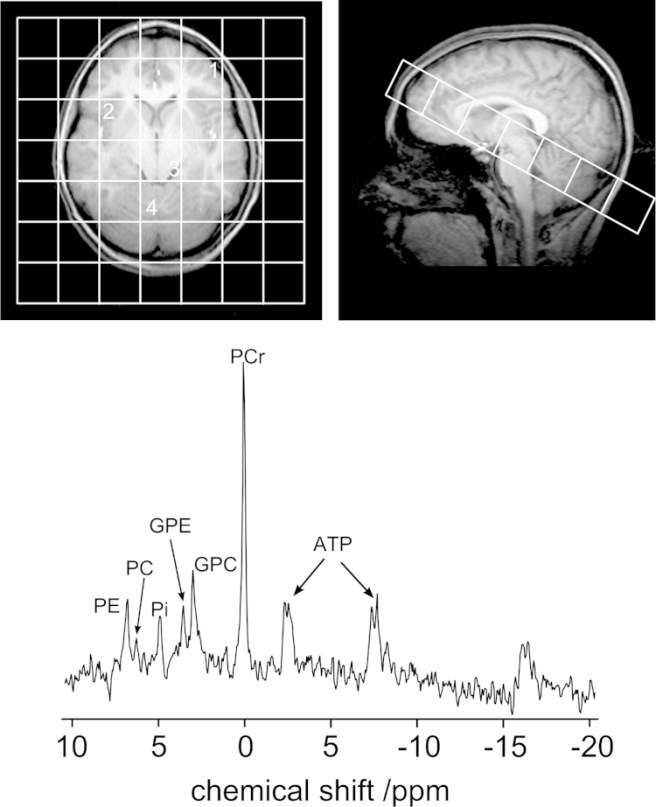

On the brain imaging side of the study, the research will be using 31P MRI-Spectroscopy.

What is 31P MRI-Spectroscopy?!?

This is a Magnetic Resonance-based form of imaging that is used to measure and quantify the function of the mitochondria. It will allow the researchers to assess whether the drug is successfully normalising the function of mitochondria in regions of the brain affected by Parkinson’s. For the participants the experience of 31P MRI-Spectroscopy will be exactly the same as having a normal MRI scan.

31P MRI-Spectroscopy. Source: PMC